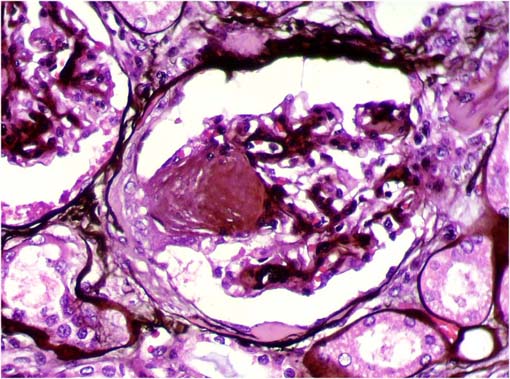

En las siguientes imágenes histológicas

de sus riñones hay una lesión patognomónica. ¿Cuál

es la enfermedad y cuál la lesión patognomónica?

Figura 1.

H&E, X400.